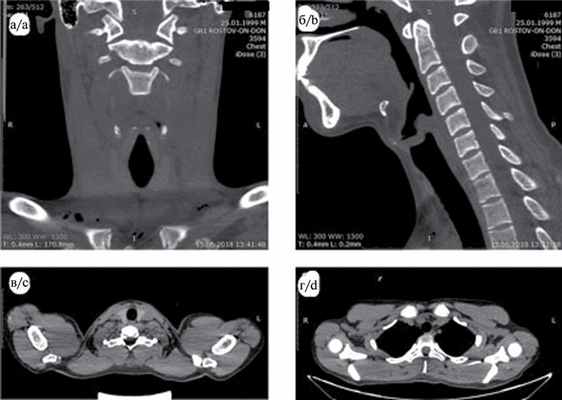

06.06.18 больному произведена КТ шеи и органов грудной клетки по программе спирального сканирования (СКТ) с толщиной среза 0,62 мм с последующей реконструкцией через 3 мм, без контрастного усиления. На серии аксиальных томограмм: органы шеи и гортань расположены обычно. Лимфоузлы шеи не увеличены. Нарушения целостности хрящей гортани и трахеи, подъязычной кости и позвонков не выявлено. В мягких тканях шеи и в верхнем отделе переднего средостения имеется скопление воздуха (рис. 1). Рис. 1. СКТ в коронарной (a), сагиттальной (б) и аксиальной (в, г) проекциях выявляет наличие воздуха в мягких тканях шеи, преимущественно справа, и в верхнем отделе переднего средостения. Очаговых или инфильтративных изменений легочной ткани не выявлено. Легочный рисунок умеренно усилен за счет расширения сосудов. Заключение: эмфизема мягких тканей шеи и верхних отделов переднего средостения.

Больному назначена антибактериальная терапия: ампициллина сульбактам 1,5 г 2 раза в день внутривенно, метронидазол 0,5% 100,0 внутривенно 3 раза в день, амикацин 500 мг 3 раза в день внутримышечно, инфузионная терапия. Все последующие дни отмечалась положительная динамика, уменьшение распространения подкожной эмфиземы, показатели крови нормализовались. На СКТ от 13.06.18 воздуха в мягких тканях шеи и средостения не обнаружено (рис. 2). Рис. 2. СКТ органов шеи (a — в коронарной, б — в сагиттальной проекции) и средостения (в — аксиальная проекция на уровне щитовидной железы, г — на уровне грудиноключичных сочленений). Воздух в мягких тканях шеи в основном не определяется. Имеется небольшое скопление воздуха в подкожной клетчатке по передней поверхности шеи, на уровне щитовидной железы. 14.06.18 больной выписан в удовлетворительном состоянии.